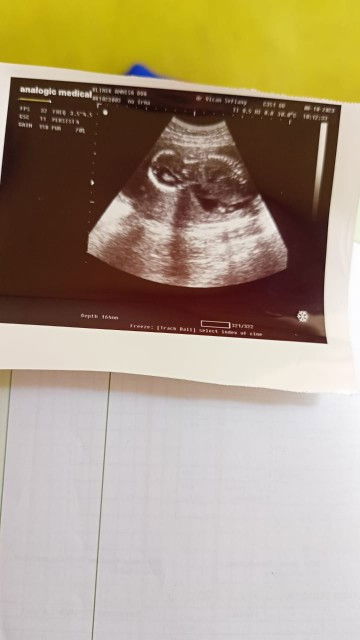

Usg pertama

Hallo bun izin tanya, kemarin aku usg hamil 18w BBJ 300gram kira² kebesaran ga ya BBJnya? Dan posisi janin seperti digambar itu sungsang atau engga ya bun?